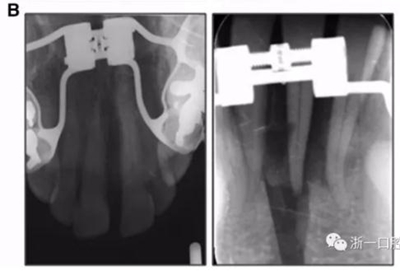

全麻下進(jìn)行上頜骨腭中縫骨皮質(zhì)劈開(kāi)及下頜正中劈開(kāi)術(shù)。手術(shù)后,用X光片檢查上頜骨和下頜骨中線切口的位置和方向。

術(shù)后第9天開(kāi)始旋轉(zhuǎn)擴(kuò)弓器,每天轉(zhuǎn)2次,每次轉(zhuǎn)90度,即擴(kuò)開(kāi)0.5mm。每隔1周進(jìn)行檢查,目標(biāo)上頜擴(kuò)開(kāi)9mm,下頜擴(kuò)開(kāi)6mm。18天后,上頜中切牙間出現(xiàn)8mm間隙。下頜出現(xiàn)6mm間隙,(于13天出現(xiàn)后,停止旋轉(zhuǎn)擴(kuò)弓器)。在擴(kuò)弓器旋轉(zhuǎn)3天后,拍片發(fā)現(xiàn)左下頜中切牙遠(yuǎn)中牙根中段有一條低密度陰影,臨床冷熱診反應(yīng)遲鈍,可能為術(shù)中損傷所致。牙體牙髓科會(huì)診,建議行根管治療,故行根管治療。